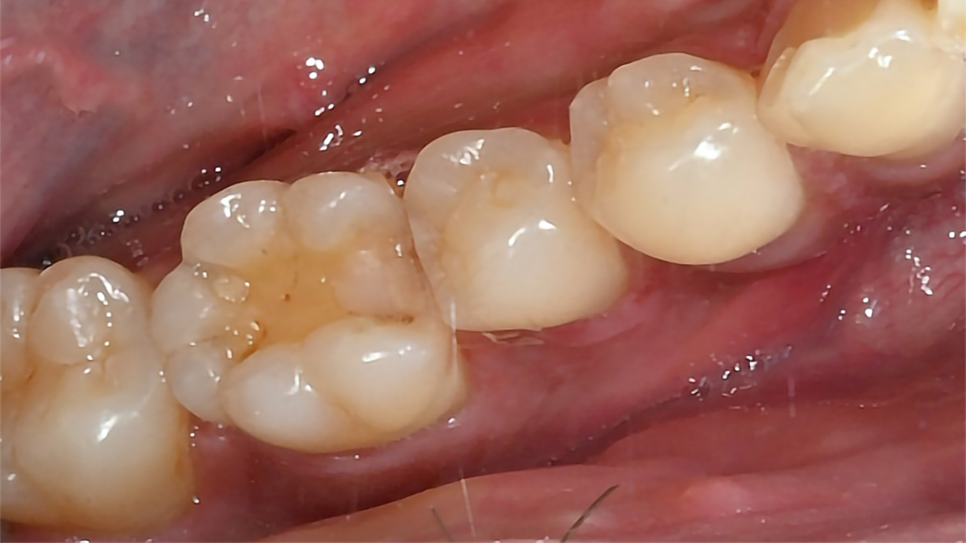

이제 약간의 손재주와 끈기가 필요합니다. 레진을 한 층 한 층 쌓아서 원래의 이상적인 치아의 모습을 만듭니다. 레진 빌드업은 치과의사의 손에서 시작하여 손에서 끝나는 치료입니다. 다음은 레진빌드업 치료결과입니다. 다른 치아와 구분이 안됩니다.

레진빌드업 치료 결과